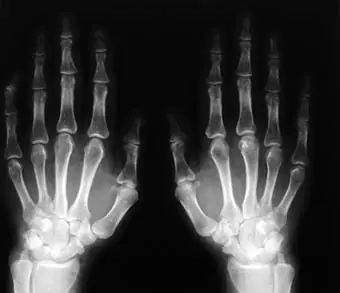

La cuestión es que casi todas las articulaciones de nuestro cuerpo están lubricadas con a un líquido viscoso, llamado líquido sinovial.

Cuando hacemos algún movimiento brusco con los dedos o nos los apretamos, su reflexión repentina hace que la articulación se estire, por lo tanto, hay más volumen y menos presión.En el líquido sinovial hay gases disueltos, como nitrógeno, oxígeno y dióxido de carbono. En los gases, a menor presión, menos solubilidad(en este caso en el líquido sinovial) y entonces escapan en forma de burbuja. El chasquido que escuchamos, es cuando la burbuja alcanza la superficie y explota.

Cuando hace frío también suenan más, porque a menor temperatura, mayor solubilidad (por eso se prefiere pescar de noche, hay más frío y más oxígeno disuelto en el agua) y por lo tanto hay más gases disueltos en el líquido sinovial.

Este líquido tarda en absorber los gases unos diez minutos, así que para volverlos a hacer sonar deberemos esperar este lapso de tiempo. Contrariamente a lo que muchos piensan, aún no hay estudios científicos concretos que asocien sonarse los huesos a complicaciones como por ejemplo artritis.Un médico llamado Donald L. Unger pasó 60 años haciéndose sonar los dedospara ver si provocaba artritis. Luego mediante estudios y sus propias articulaciones como testigos,demostró que sonarse los dedos no provoca artritis y fue galardonado con el Premio Ig Nobel de Medicina.